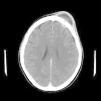

El Pott's puffy tumor (PPT) es una rara entidad que en la actualidad representa un abombamiento del cuero cabelludo asociado a un absceso subperióstico y a una osteomielitis craneal, pudiendo acompañarse o no de infección intracraneal. Suele asociarse a la sinusitis frontal, tratándose de una complicación típica, aunque poco frecuente de la misma. Por su parte las osteomielitis causadas por Actinomyces son raras y suelen tener lugar a nivel mandibular, no encontrándose apenas casos de osteomielitis craneal causada por este género bacteriano, en especial tras traumatismo craneoencefálico. Presentamos un caso especialmente poco usual al tratarse de un PPT frontal tras traumatismo cerrado, con componente intracraneal y en el que tras cirugía se aisló Actinomyces como copartícipe de dicha infección, junto con Fusobacterium y Propionibacterium.

Pott's puffy tumour (PPT) is a rare entity that involves scalp swelling associated with subperiosteal abscess and cranial osteomyelitis, occasionally accompanied by intracranial infection. It is usually affiliated with frontal sinusitis, which is a typical but infrequent complication. On the contrary, Osteomyelitis by Actinomyces is rare and usually occurs at the mandibular level, with very few cases of cranial osteomyelitis caused by this bacterial specie, especially after traumatic brain injury. We report an exceptionally unusual case of a PPT frontal tumor after blunt trauma (closed head injury), with an intracranial lesion whereby Actinomyces was isolated after surgery, as a co-participant of the mentioned infection besides Fusobacterium and Propionibacterium.